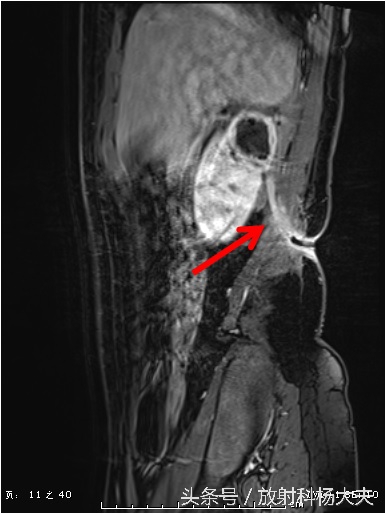

这个囊性病变到底是什么?囊性肿瘤?有无办法继续明确呢?有!那就是MRI,除了进一步明确,还能更清楚的显示窦道的走行。下图这个序列,叫DWI,红箭所示的白白的东西,证明这是一个脓肿!

终于搞清楚了,原来一个月前的腰痛,是肾脏的脓肿,而且MRI上还能清晰的显示脓肿破口的位置,下图中黄箭所示(红箭为脓肿)。